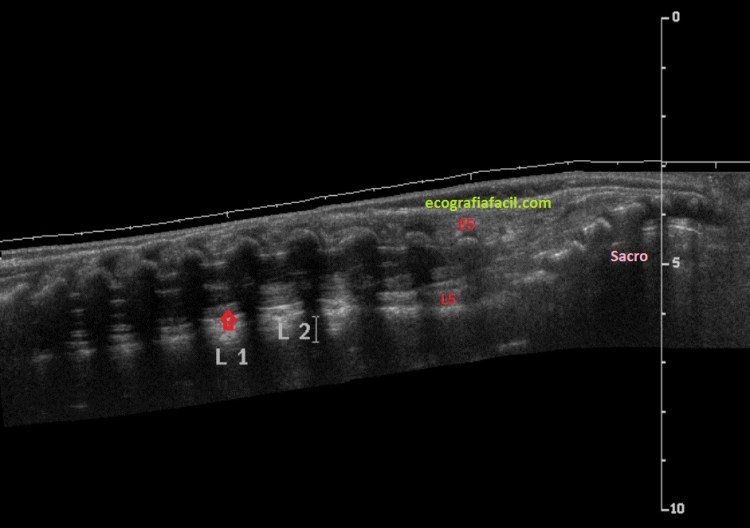

Finalmente realizaremos una vista panorámica como esta donde poder ver toda la anatomía, resulta esclarecedora:

Finally we will perform a panoramic view like this where you can see the entire anatomy, it is enlightening:

Le tengo tanto cariño a esta imagen…En ella ves lo punto claves, sacro, última espinosa y por tanto localización del cuerpo de L5…final del cono medular…preciosa…

I am so fond of this image … In it you see the key point, sacral, last thorny and therefore location of the body of L5 … end of the spinal cone … beautiful …